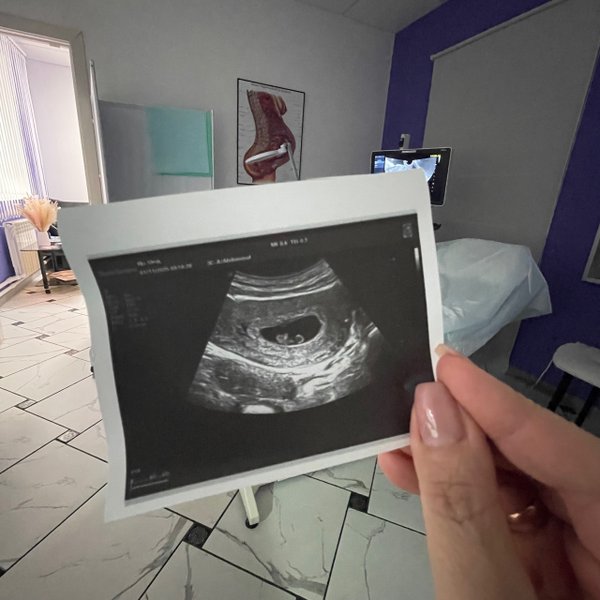

Кажется, еще вчера тест показал две полоски, а сегодня мы уже рассматривали ручки и ножки на мониторе ВАШЕ крошечное солнышко‼️ PS.. группа поддержки в виде ️бабушки и мужа на осмотре . были --- Бородулина Наталья (Врач УЗИ, Косметология) (08.01.2026): Давайте поиграем‼️ Угадайте по фото #УЗИ, кто тут ( Шутка, конечно, рано еще Но верить в чудеса можно уже сейчас). Поделитесь в комментариях своими первыми #фото «горошков», «фасолинок» и «эмбриончиков» устроим галерею самого начала жизни ️

УЗИ диагностика. ‼️По записи Без очереди ⏰Ежедневно с 10:00 до 17:00 ️Перерыв с 13:00 до 14:30 ️Суббота с 10:00 до 15:00 ‼️Воскресенье ВЫХОДНОй --- Бородулина Наталья (Врач УЗИ, Косметология) (27.10.2025): Магия Первой Встречи: #УЗИ до 11 недель и Тайная Жизнь Внутри Вас 1. Он уже не «точка»‼️ У него уже есть головка, тельце и даже видны зачатки ручек и ножек, которые сейчас больше похожи на плавнички. 2. Он не просто лежит — он ДВИГАЕТСЯ‼️ Да-да, вы не ослышались! Уже с 7—8 недель малыш начинает совершать свои первые, еще хаотичные, но такие… — Читать дальше

трогательные движения. Он может взмахивать ручками, подпрыгивать, отталкиваться от стенок матки. ️ Возьмите с собой самого близкого человека. Разделите эти незабываемые эмоции с партнером. Это #УЗИ — ваш первый семейный портрет. Тот самый снимок, который вы унесете с собой, будет самым ценным кадром. На нем — не просто пятнышко. На нем — вся ️вселенная, уместившаяся в несколько сантиметров.

Бородулина Наталья (Врач УЗИ, Косметология) (19.12.2024): Милое видео.. спасибо «режиссеру».. будущему папе) На #узи по беременности можно с мужем Беременность 6 недель ️ Предварительная запись ⤵️ по тел.

Бородулина Наталья (Врач УЗИ, Косметология) (29.11.2024): Малыш с «шариком» ️ долгожданная беременность..маленькое счастье да-да, даже в такой маленький срок, сердечко УЖЕ слышно

PS.. группа поддержки в виде ️бабушки и мужа на осмотре . были